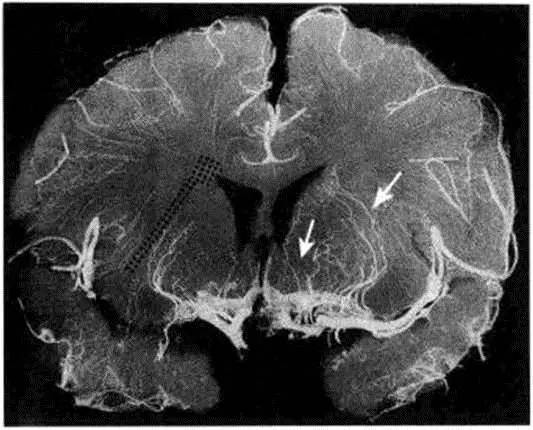

图2 大脑半球冠状面显示大脑中动脉主干及其分支——豆纹动脉

由高血压引起的脂质透明样变性和中膜过度增生主要累及:①大脑中动脉的豆纹动脉穿通支(图2);②大脑前动脉的穿支,通常指Heubner动脉(图3和图4);③前交通动脉发出的穿通支(图5和图3);④大脑后动脉发出的丘脑穿通动脉和丘脑膝状体穿支(图3);⑤由基底动脉发出,到达脑桥、中脑和丘脑的旁中央穿通支。在某些情况下,母动脉粥样硬化斑块形成或穿支口微小粥样硬化斑块会堵塞穿通动脉(图6)。动脉粥样硬化性穿支闭塞的累及部位与脂质透明样变性有相同之处,但同时前者还可累及较大的动脉(例如颈内动脉的分支脉络膜前动脉以及大脑后动脉发出的丘脑膝状体动脉)。

图4 冠状位尸解血管造影显示大脑前动脉(白箭头)的分支。黑点区域(图片左侧)为内交界区。(From Pullicino P:Lenticulostriate arteries. In Bogousslavsky J,Caplan LR(eds):Stroke Syndromes,2nd ed. Cambridge:Cambridge University Press,2001,pp 428-437.)